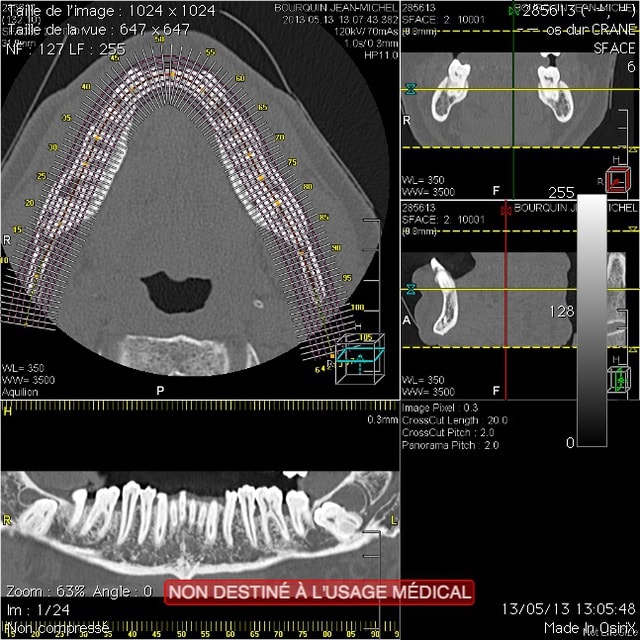

Patient d'environ 45-50, consultation fortuite, voilà ce que je trouve.

D'un côté, la situation est juste un peu tendue : la dent repose franchement sur le NDI.

De l'autre, les deux racines le pince littéralement.

Tout cela est asymptomatique bien entendu.

Quelle conduite tiendriez-vous dans ce cas ?

(Les coupes sont toutes deux du même côté, l'autre me semble moins discutable)

A dire vrai, je suis en train d'envisager le fait de gérer ça, en étudiant la possibilité de séparer les racines qui font étau. Pour cela il me faudra une reconstruction 3D bien proprette.

Comme je suis pas au cab, et que je suis en train de bosser sur le scan, j'ai mis tout ce dont je disposais... Cela dit, faire cette chir sans 3D, "à la retro" (aux deux sens du terme), c'est criminel.

Tiens, voilà du boudin ;) :

- CT 1 et 2 : le côté gauche, LE gros morceau

- CT 3 et 4 : le côté droit, dont on peut tout de même se demander si le nerf ne sera pas un peu adhérent à l'apex.